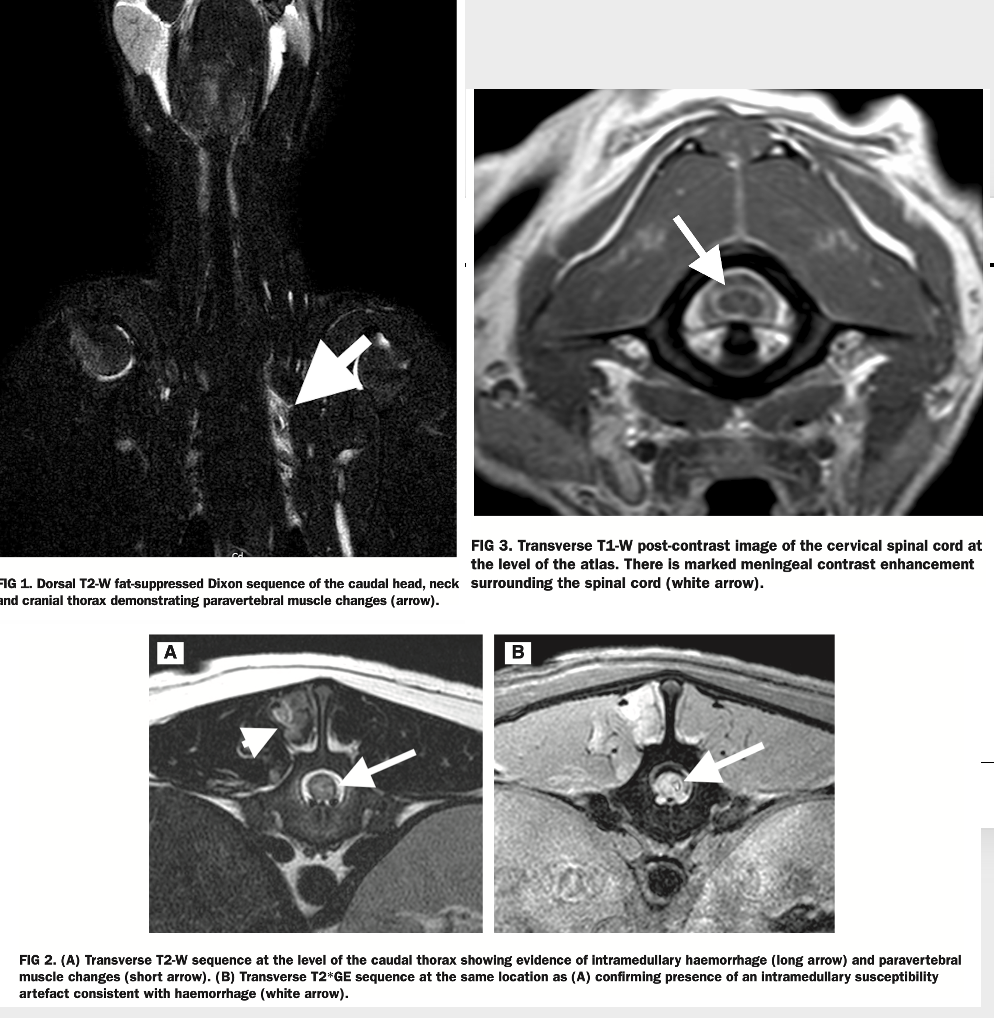

List typical MRI changes and frequency in dogs with SRMA

Jones BA et al. Magnetic resonance imaging findings in dogs with SRMA in the UK and their clinical significance: 53 cases (2013–2021). (JSAP, accepted 2025).

• 73% of dogs had abnormalities

• paravertebral muscle changes (30/53; 56.6%)

• meningeal contrast enhancement (13/41; 31.7%)

• spinal cord parenchymal T2-W hyperintensity (15/53; 28.3%)

• Haemorrhage was observed in five of 53 (9.4%)

• Fifty-two (98.1%) dogs survived to discharge

• Relapse occurred in nine of 29 (31.0%)

What is evident on the MRI?

• intradural, extramedullary hemorrhage

• here due to SRMA